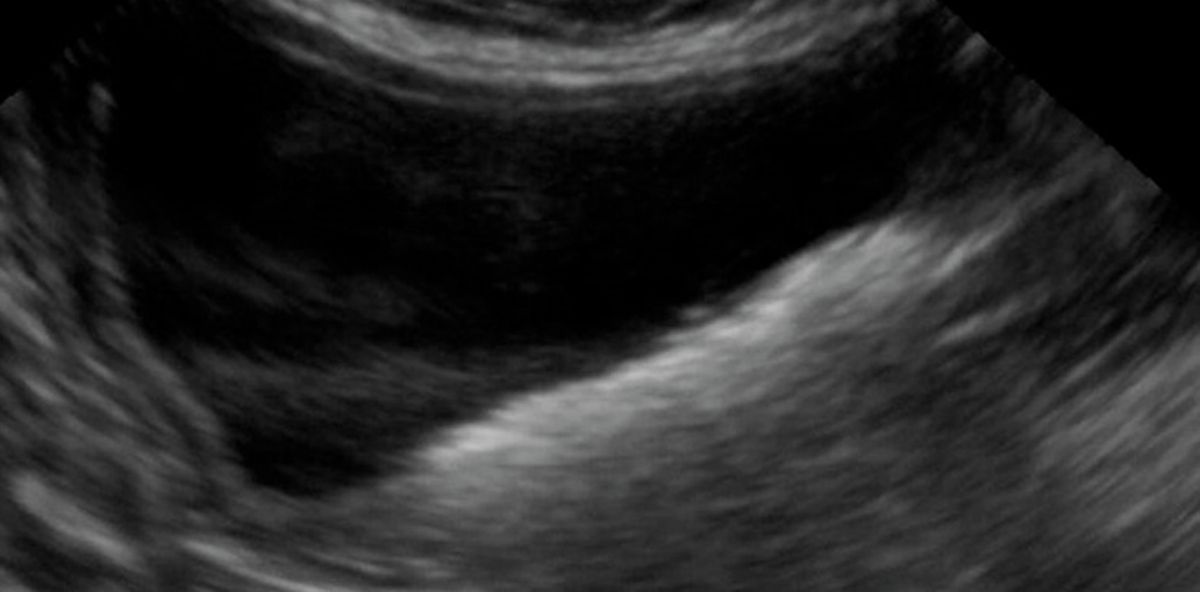

Floating debris in the urinary bladder of a cat Drijvend debris in de Debris In Cat Urine particles in the urine in cats. What is particles in the. cats have highly concentrated, acidic urine that predisposes them to form stones of the urinary tract, especially when certain. if your cat suddenly becomes less active or loses interest in their meals, it could be a sign of an underlying urinary. In some cats, struvite bladder. Debris In Cat Urine.

From www.youtube.com